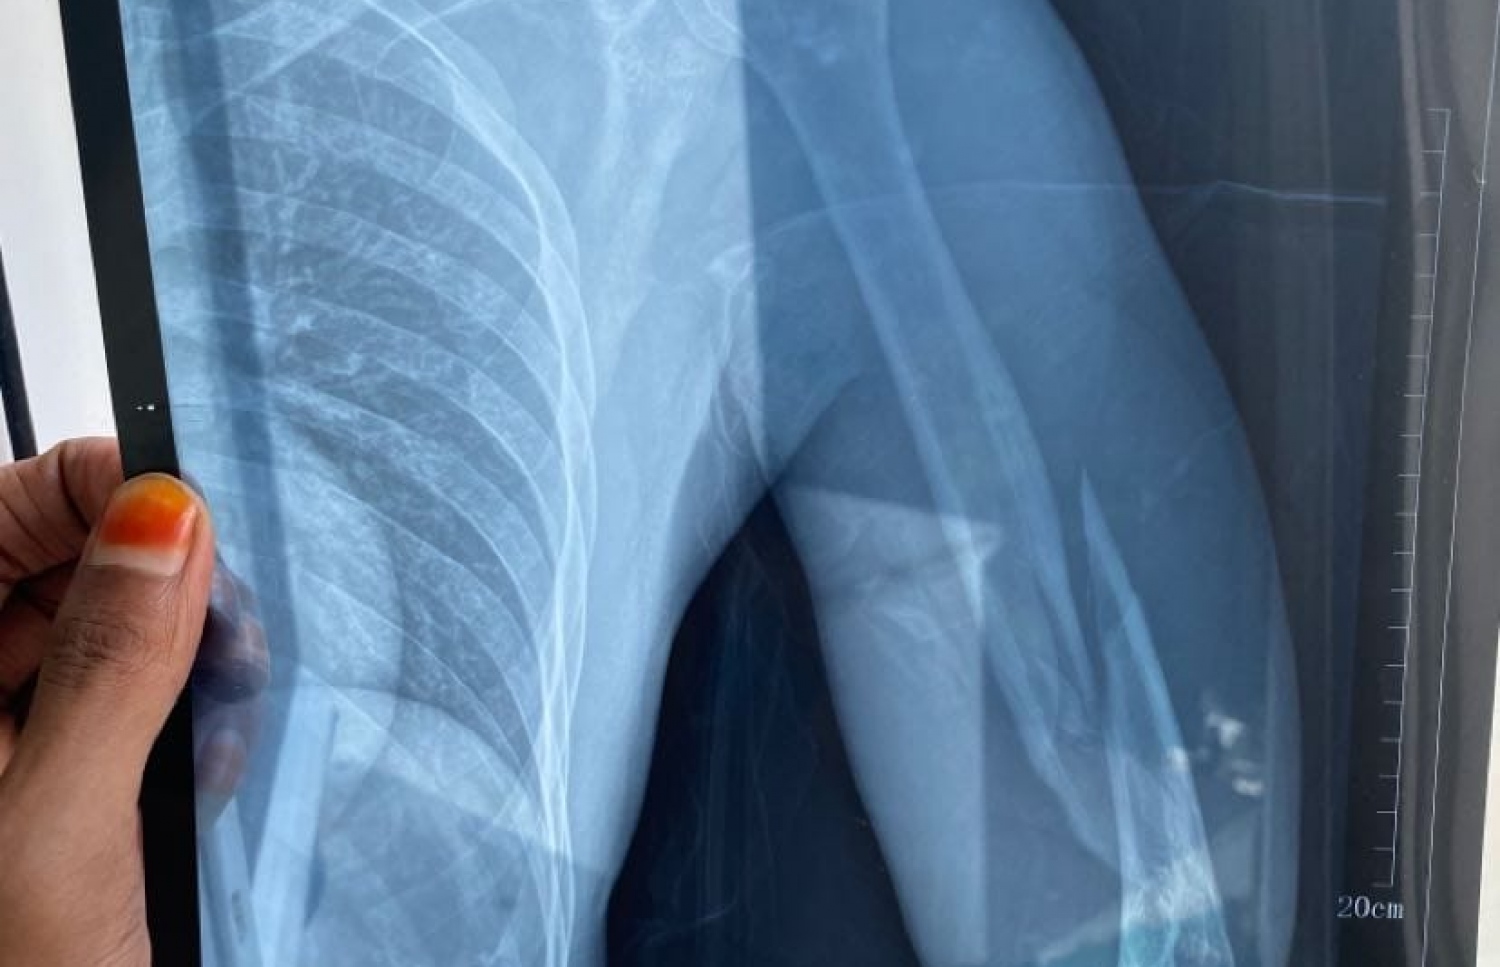

ފަތޯގެ އަތުގެ އެކްސްރޭއިން ފެންނަ ގޮތުގައި އޭނާގެ ވައަތުގެ ކޮނޑުހުޅާއި އުޅަނބޮއްޓާ ދެމެދުން ވަނީ ބިންދައިގެން ގޮސްފަ އެވެ. އެ އަތް އޮޕަރޭޝަންކޮށް ބޮލްޓު އަޅަން ޖެހިފައިވާ ކަމަށް ޑޮކްޓަރުންނާ ހަވާލާދީ އޭނާ ބުންޏެވެ.

ލަވަކިޔުންތެރިޔާ ފަތޯގެ އަތުގެ އެކްސްރޭ: ވައަތުގެ އުޅަނބޮއްޓާއި ކޮނޑުހުޅާ ދެމެދުން ވަނީ ބިނދިފައި.

ލަވަ ކިޔުމުގެ އިތުރުން ގިޓާ ވެސް ކުޅޭ ފަތޯ ބުނީ އަތުގެ ކަށިގަނޑު އެއްކޮށް ވަކިވެފައި ވާތީ، ނާރުގެ މައްސަލަތައް ދިމާވެ އަތުގެ ހަރަކާތް ގެއްލިދާނެ ކަމުގެ ކަންބޮޑުވުން އެބަ އޮތް ކަމަށެވެ. މިހާރު ވެސް އަތް ދުޅަވެ، އެ އަތުގެ އިނގިލިތަކުން ހަރަކާތް ކުރަން ދަތި ކަމަށް އޭނާ ބުންޏެވެ.